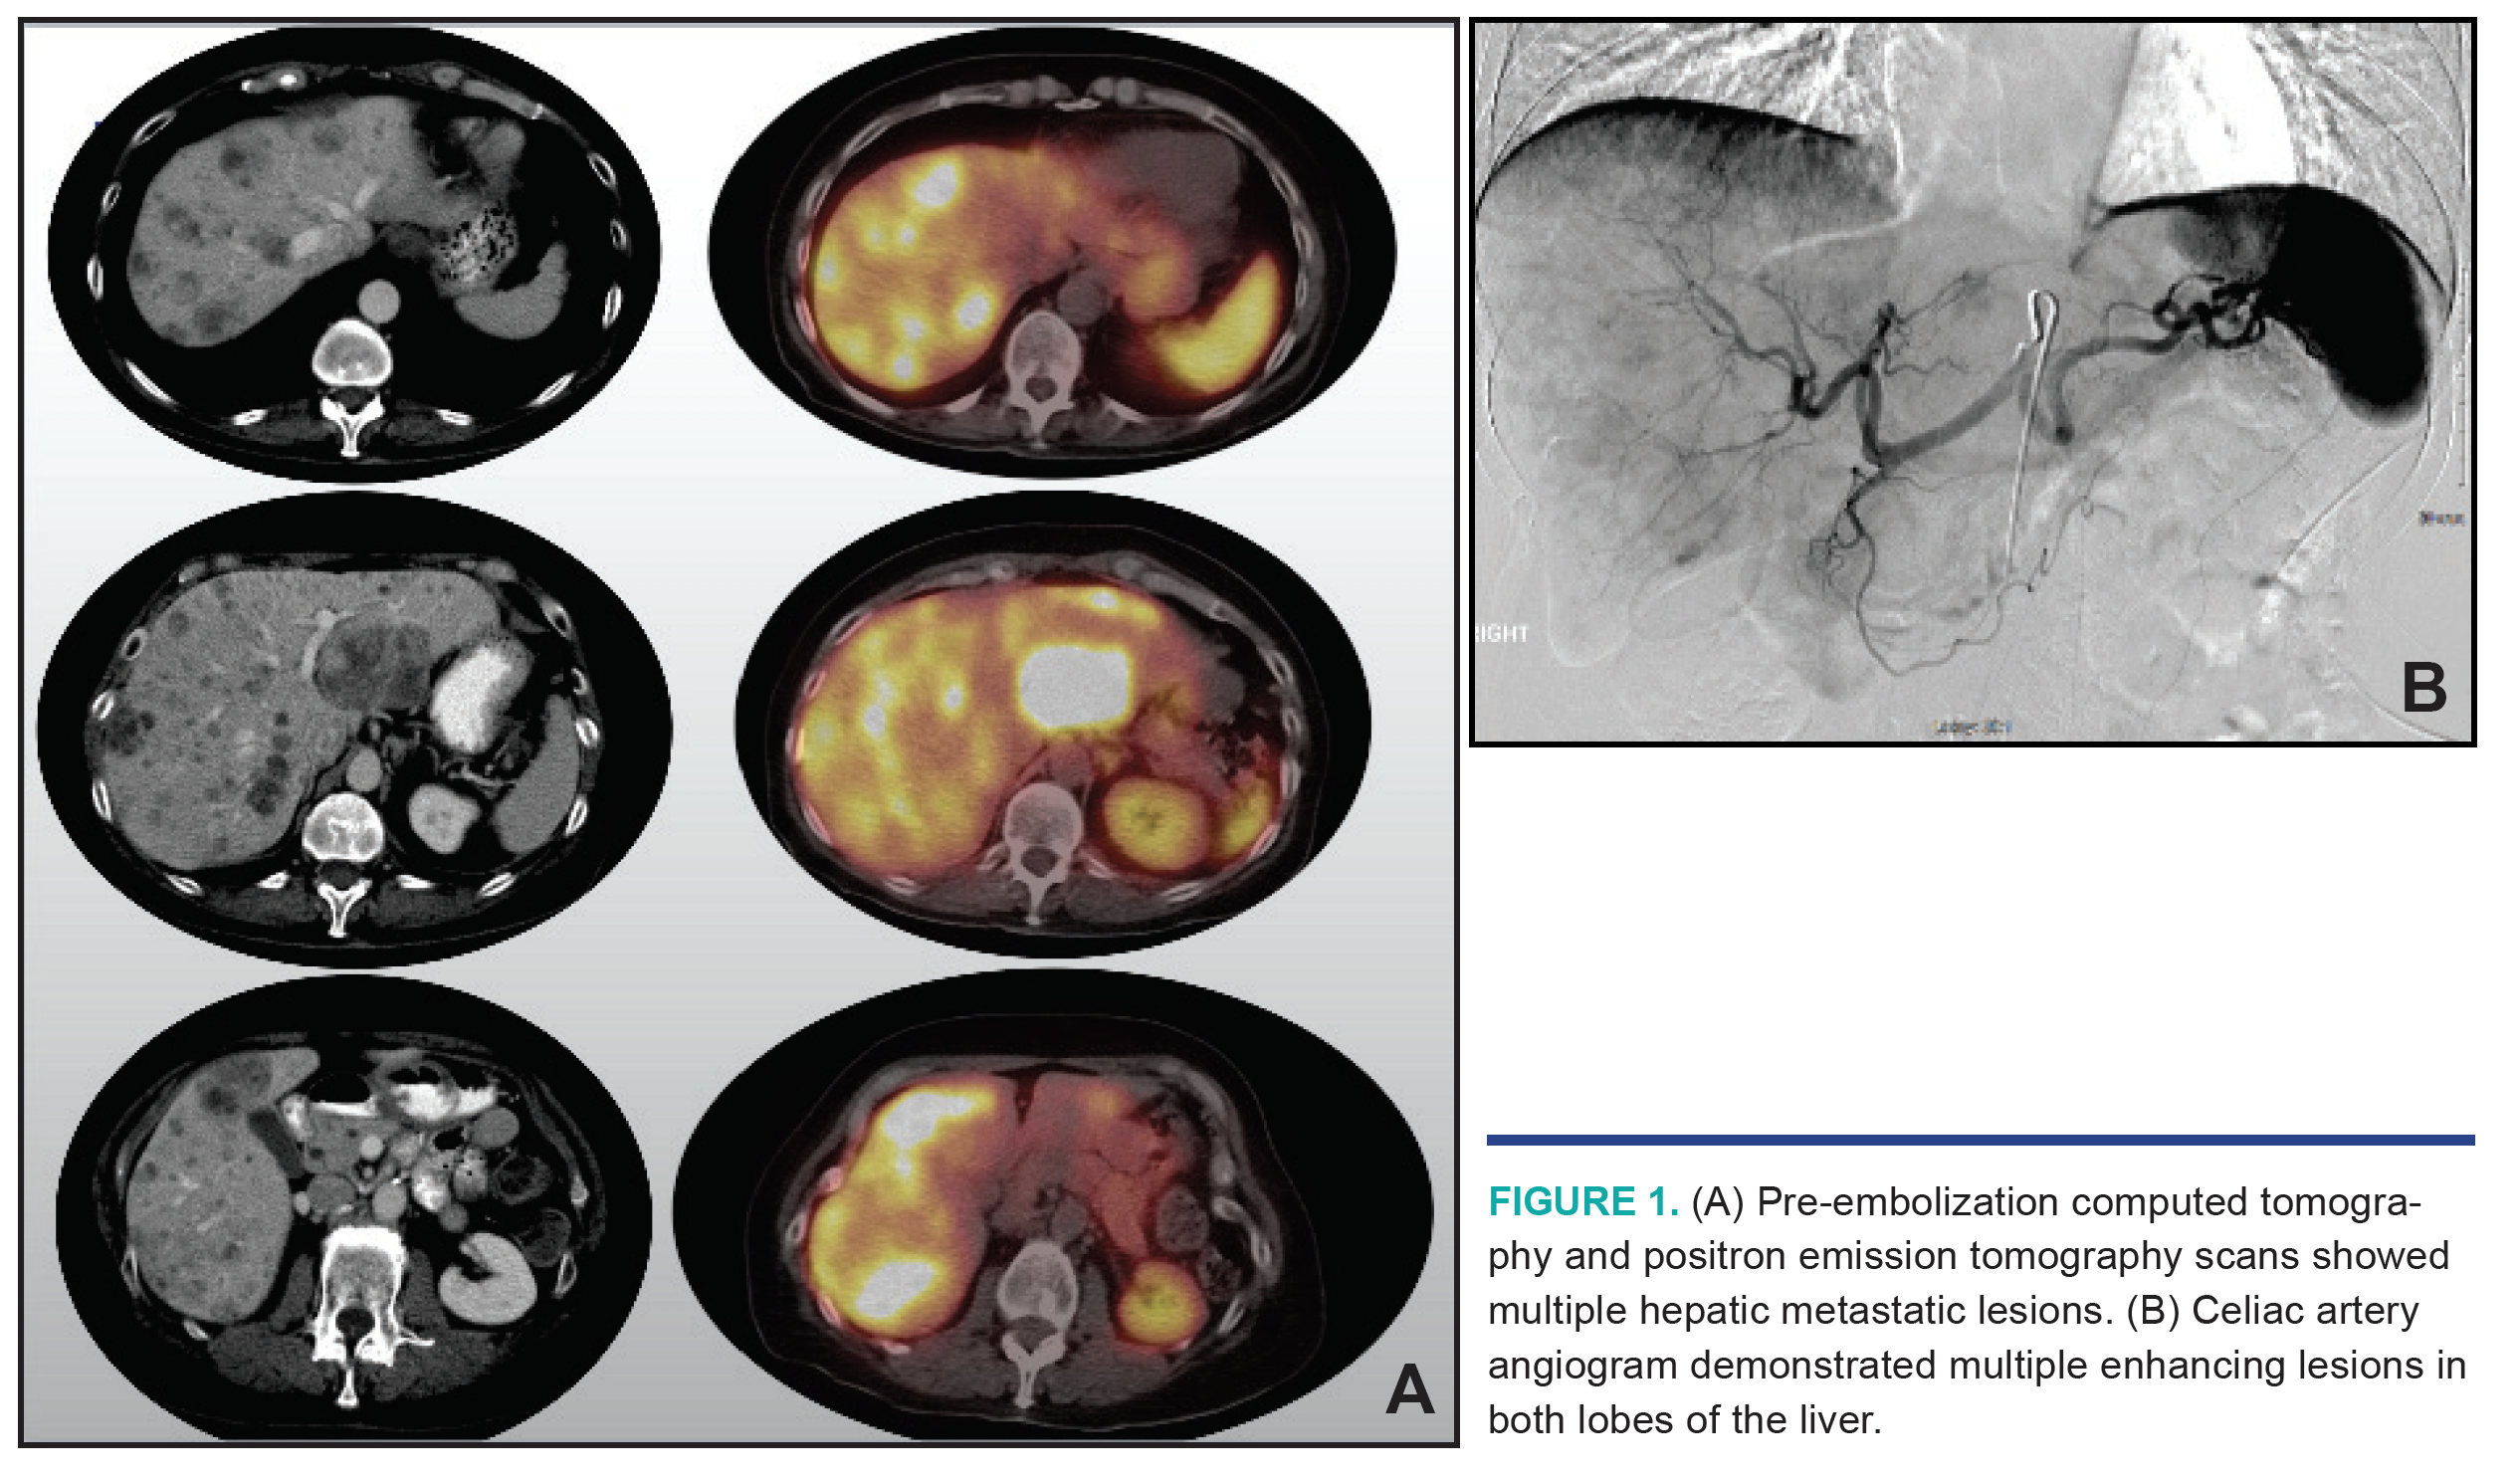

A 63-year-old woman presented with diarrhea and unintentional weight loss. Positron emission tomography (PET) and computed tomography (CT) of the abdomen and pelvis showed multiple hepatic metastatic lesions and a soft tissue mass along the terminal ileum. Liver biopsy confirmed a low-grade neuroendocrine tumor (antigen Ki-67, 1.9%). She was initiated on octreotide and everolimus. A few months later, a PET-CT scan with Gallium-68 dotatate radiotracer demonstrated a somatostatin-analog avid nodule projecting to the terminal ileum and multifocal sites of intense somatostatin-analog localization within both lobes of the liver consistent with hepatic metastases (Figures 1A and 2A; Video 1). Due to the patient’s progressive disease, she underwent bland hepatic embolization (Figure 1B) of the left lobe (Figure 2B; Video 2) using 250 micron Embozene microspheres (Varian Medical Systems) followed by right hepatic lobe bland embolization (Figure 2C; Video 3) using 250 micron Embozene microspheres a few months later. She then underwent resection of the primary site at the terminal ileum, and is now clinically asymptomatic.